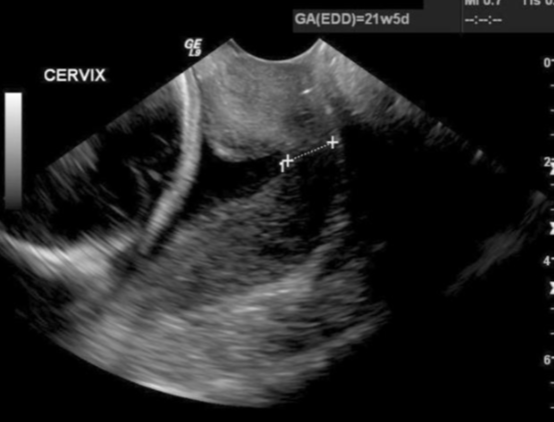

What type of U/S is best able to accurately determine cervical length?

Transvaginal

Transvaginal Cervical U/S

have pt empty bladder

lithotomy position

insert trdx or have pt insert

align trdx w/ endometrial stripe in longitudinal plane

obtain a sagittal view of the cervix, w/ the long axis view of echogenic endocervical musoca along the length of the canal

lengthen out the cervix and measure from internal os to external os

observe cervix for dynamic changes

Incompetent Cervix

premature opening or shortening of the cervix that may lead to fetal loss

may “funnel” (dilation of the internal os)

sign of cervical incompetence

dilation of the internal part of the cervical canal and reduction of the cervical length

>50% funneling before 25 weeks is associated w/ approx. 80% risk of preterm delivery